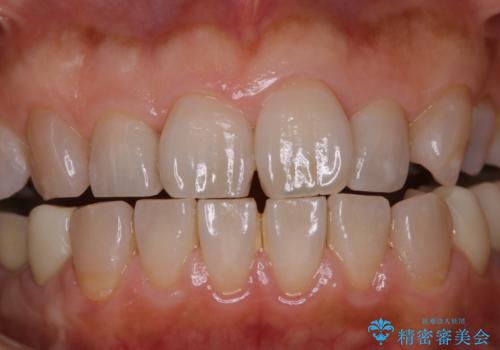

着色・ステイン除去をPMTCで

担当医 歯科衛生士